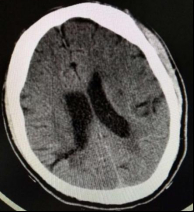

患者于当日23:50送达本院急诊抢救室。来院时神志不清,GCS评分7分,血压132/87 mmHg(1 mmHg=0.133 kPa),心率90次/min,呼吸22次/min,脉搏92次/min,血氧饱和度96%,血糖6.7 mmol/L。查体见面色红润,舌体咬破。两肺呼吸音清,未闻及干湿性啰音,心律齐,无明显病理性杂音,腹平软,压痛反跳痛难以配合,两侧病理征未引出。2019-01-02 23:58心电图示窦性心律,ST段改变(图 1A)。2 h后复查心电图示窦性心动过缓,ST-T改变,左室高电压、心电轴左偏,Ⅰ、Ⅴ5、Ⅴ6导联ST段呈水平型、下斜型压低,0.05~0.1 mV,Ⅴ1、Ⅴ2、AVR呈水平型抬高(图 1B)。(2019-01-03 00:15)床边检测cTnT 0.014 ng/mL,D-二聚体 > 10 000 ng/mL,NT-pro BNP 20 600 ng/L。2 h后复查cTnI 0.049 ng/mL。生化示肌酐284 μmol/L,其余指标未见明显异常。头颅CT示右侧颞枕叶条片灶,局部似与右侧脑室后角相连,脑裂畸形:合并灰质异位?软化灶合并脑穿通畸形?(图 2)。胸部CT示心脏增大、肺动脉高压,肺动脉主干增宽4.0 cm,心包前部少许积液。床边心超示:左室壁运动欠协调,室间隔运动稍减弱,主动脉瓣反流(轻度),EF为52%。患者入院后烦躁不安,先后予镇静、抗癫痫等治疗。因患者D-二聚体升高明显,胸部CT示肺动脉增宽明显、肺动脉高压,考虑存在肺栓塞可能; 另一方面,患者血压呈进行性上升,D-二聚体升高,CT示心包前部少许积液,故主动脉夹层亦不能除外,需行动脉造影明确,但因患者肌酐异常,存在慢性肾衰竭,行增强CT检查需注射造影剂,可能进一步加重肾损害,故家属拒绝。2019-01-03 07:00患者神志转清,诉有头晕,无胸痛,血压持续波动在200/100 mmHg左右,予镇静、降压效果均较差,病情反复告知家属,家属商议后最终同意行CTA检查。13:05行胸部增强+肺CTA示主动脉弓夹层(De Bakey I、Stanford A型),肺动脉高压(图 3)。最终患者诊断主动脉夹层(De Bakey I、Stanford A型)明确,因本院手术条件所限,当天即予转上一级医院手术治疗。

| 图 2 患者头颅CT图像(右侧颞枕叶条片灶) |